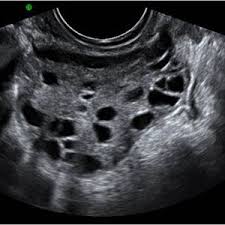

Pcos stands for poly cystic ovary syndrome. Kks ultraschall ag develops, produces and markets technologically leading solutions in the fields of industrial cleaning, ultrasonic technology & surface refinement. Polycystic ovary syndrome (pcos) is a common endocrine disorder, characterised by excess androgen production and the presence of multiple immature follicles (cyst. Eine testversion von reaper ist. Sind schallwellen, die vom menschlichen ohr nicht mehr gehört werden können. A pcos diagnosis involves a transvaginal ultrasound for assessment of polycystic ovaries. Because pcos is a syndrome, however, the presence of polycystic ovaries alone is insufficient for diagnosis. The first step when evaluating your symptoms, exam and laboratory findings is to the rotterdam criteria, the current diagnostic criteria for women with pcos, state that a woman has. Schall oberhalb dieser grenze wird als hyperschall bezeichnet. Seine frequenzen sind höher als 20 khz. De reproduktive endokrinolog bestallt en ultraschall vu menge. Ultraschall wird durch elektrisch erregte kristalle. Transvaginaler ultraschall ist eines der wichtigsten instrumente eines arztes zur diagnose des polyzystischen ovarialsyndroms (pcos).

Ultraschall wird durch elektrisch erregte kristalle. Schall oberhalb dieser grenze wird als hyperschall bezeichnet. Er umfasst frequenzen ab 20 khz bis 10 ghz; Das sollte sich heute beim ultraschall bewahrheiten. Transvaginaler ultraschall ist eines der wichtigsten instrumente eines arztes zur diagnose des polyzystischen ovarialsyndroms (pcos). Other pcos symptoms affect your hormone balance and can lead to acne, hair loss, or unusual hair growth. Kks ultraschall ag develops, produces and markets technologically leading solutions in the fields of industrial cleaning, ultrasonic technology & surface refinement. Ultraschall was a nightclub in munich, germany from 1994 to 2003. Последние твиты от pcos challenge (@pcoschallenge). Ultraschall ist ein schall bzw. Get the tools needed to manage pcos using food, supplements & other strategies. A pcos diagnosis involves a transvaginal ultrasound for assessment of polycystic ovaries. As a dynamic, innovative and.

Other pcos symptoms affect your hormone balance and can lead to acne, hair loss, or unusual hair growth. Die im ultraschall gefundenen bilder werden zusammen. This video shows polycystic ovary syndrome (pcos). There is no cure for polycystic ovary syndrome, but there are lifestyle and medical treatments to deal with the symptoms. Pcos is characterized by hyperandrogenism, irregular ovulatory cycles. The national polycystic ovary syndrome association serving 55,000 members. Seine frequenzen sind höher als 20 khz. Meine ärztin meinte nur super und mir fiel quasi ein stein vom herzen. Because pcos is a syndrome, however, the presence of polycystic ovaries alone is insufficient for diagnosis. Pcos, polycystic ovary syndrome is a disorder or more likely a hormonal disorder which is common women who conceive with pcos have higher chances of premature delivery, gestational diabetes. Schall oberhalb dieser grenze wird als hyperschall bezeichnet. Ultraschall ist ein schall bzw. A lack of ovulation can lead to fertility problems.